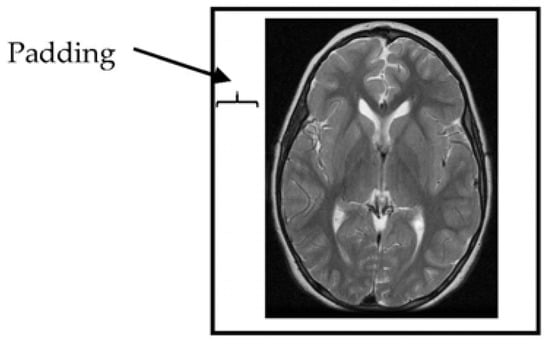

The provided MRI brain slices were collected from two scanners with different spatial resolutions. To enable the use of the full set without bias, the MRI scans were resized to 512 × 512 pixels. All algorithms developed in this study were implemented on squared slices. When the dimensions of the given MRI slices were changed to a square ratio, care was taken to maintain the ratio of voxels to pixels (e.g., pixel spacing). The MRI slices were then resized by adding additional columns from the left and right and additional rows from the top and bottom portions of the MRI slice until the slice size became 512 × 512 pixels in resolution (Figure 2).

Figure 2. Padding of MRI brain image margins by zeros.